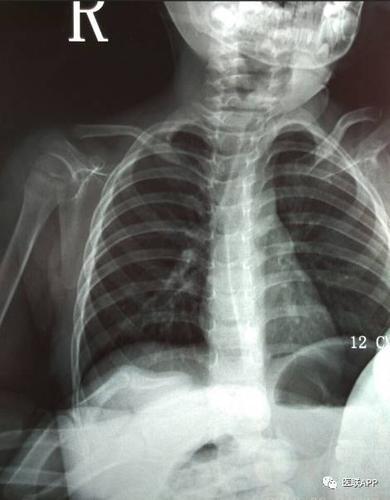

锁骨骨折

小儿锁骨青枝骨折一例

【求助】五个月大婴儿不慎跌落导致右侧锁骨青枝骨折